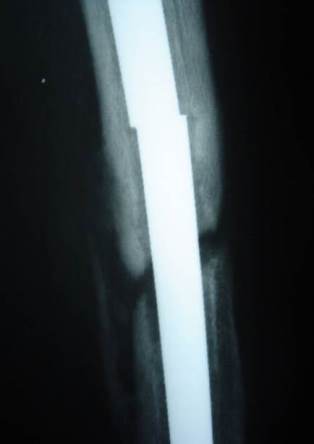

Nail parts after removal

Middle part of the nail was removed by a small break in the lateral cortex.

Distal part of the nail was removed by a hole distally in the lateral cortex then pushed by a drill pit and pulled through the medulla by an intestinal clamp.